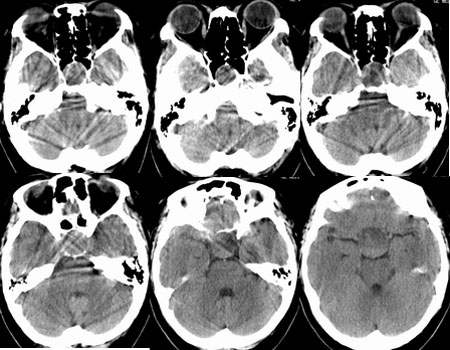

鞍区垂体窝内见一巨大类椭圆性软组织块影,前后床突受压移位、变薄,鞍底凹陷,应当能明确诊断垂体瘤。不过最好能做个mri看看视神经受累情况

蝶鞍内圆形密度不均匀,包膜完整肿块影,前床突与鞍底变薄.

意见:垂体大腺瘤.

本病例单凭ct检查是很难定位准确的,是鞍上病变侵犯鞍内、还是鞍内病变向鞍上生长?

1、如果鞍内肿瘤突破鞍隔,向鞍上生长,考虑垂体腺瘤,其典型表现是肿瘤呈"8"字征。

2、如果是鞍上肿瘤侵犯鞍内,要考虑鞍区脑膜瘤、生殖细胞瘤、实性颅咽管瘤(多为囊性、少数也可实性)、转移瘤、垂体柄胶质细胞瘤。